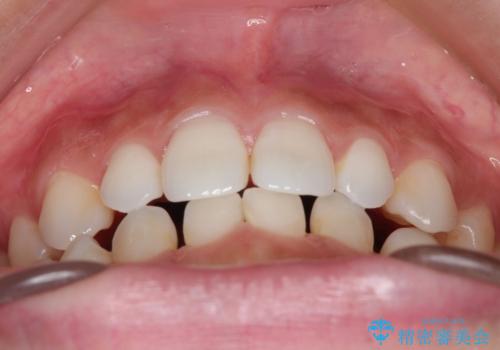

- 空隙歯列を主訴に来院された患者様です。

ばらけている空隙を一箇所に集めながら咬合や正中を改善して最後に補綴治療を行なっています。

右上の臼歯クロスバイトは骨格生のため、そのままにしています。